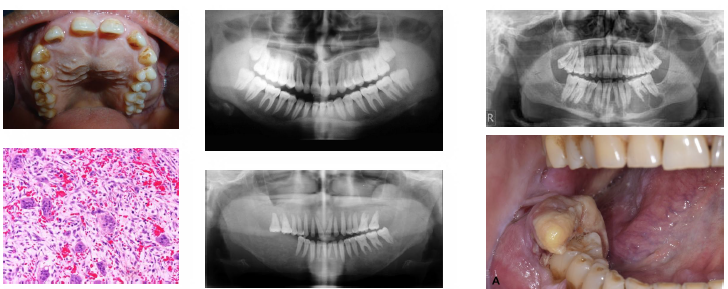

hyperparathyroidism clinical radiographic features

•"Stones bones groans" classic symptom pattern

•Renal stones due to hypercalcemia levels

•Ground glass bone with lamina dura loss

•Brown tumors cause jaw radiolucencies

•Bone and root resorption may be evident

hyperparathyroidism overview

excess PTH increases serum calcium levels

primary due to tumor or gland hyperplasia

secondary due to chronic hypocalcemia states

renal failure common cause of secondary type

leads to bone resorption and systemic effects